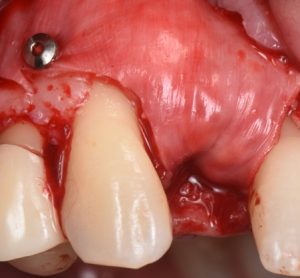

This video demonstrates implant placement in the esthetic zone combined with simultaneous guided bone regeneration (GBR). The case focuses on surgical decision-making, specifically how to determine when a staged approach is indicated versus when simultaneous implant placement and GBR can be predictably performed.

The procedure is presented step by step, including flap design and management, defect assessment, membrane selection and stabilization, flap advancement, and suturing techniques. Emphasis is placed on achieving tension-free closure and maintaining hard and soft tissue contours critical for esthetic success.